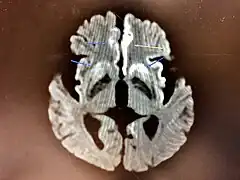

The symptoms of CJD are caused by the progressive death of the brain's nerve cells, which are associated with the build-up of abnormal prion proteins forming in the brain. When brain tissue from a person with CJD is examined under a microscope, many tiny holes can be seen where the nerve cells have died. Parts of the brain may resemble a sponge where the prions were infecting the areas of the brain.[17]

Histopathology

Spongiform change in CJD

Testing of tissue remains the most definitive way of confirming the diagnosis of CJD, although it must be recognized that even biopsy is not always conclusive.[51]

In one-third of people with sporadic CJD, deposits of "prion protein (scrapie)", PrPSc, can be found in the skeletal muscle and/or the spleen.[52] Diagnosis of vCJD can be supported by biopsy of the tonsils, which harbor significant amounts of PrPSc; however, biopsy of brain tissue is the definitive diagnostic test for all other forms of prion disease. Due to its invasiveness, biopsy will not be done if clinical suspicion is sufficiently high or low. A negative biopsy does not rule out CJD, since it may predominate in a specific part of the brain.[53]

The classic histologic appearance is spongiform change in the gray matter: the presence of many round vacuoles from one to 50 micrometers in the neuropil, in all six cortical layers in the cerebral cortex or with diffuse involvement of the cerebellar molecular layer.[54] These vacuoles appear glassy or eosinophilic and may coalesce. Neuronal loss and gliosis are also seen.[55] Plaques of amyloid-like material can be seen in the neocortex in some cases of CJD.[56]

However, extra-neuronal vacuolization can also be seen in other disease states. Diffuse cortical vacuolization occurs in Alzheimer's disease, and superficial cortical vacuolization occurs in ischemia and frontotemporal dementia. These vacuoles appear clear and punched-out. Larger vacuoles encircling neurons, vessels, and glia are a possible processing artifact.[53]